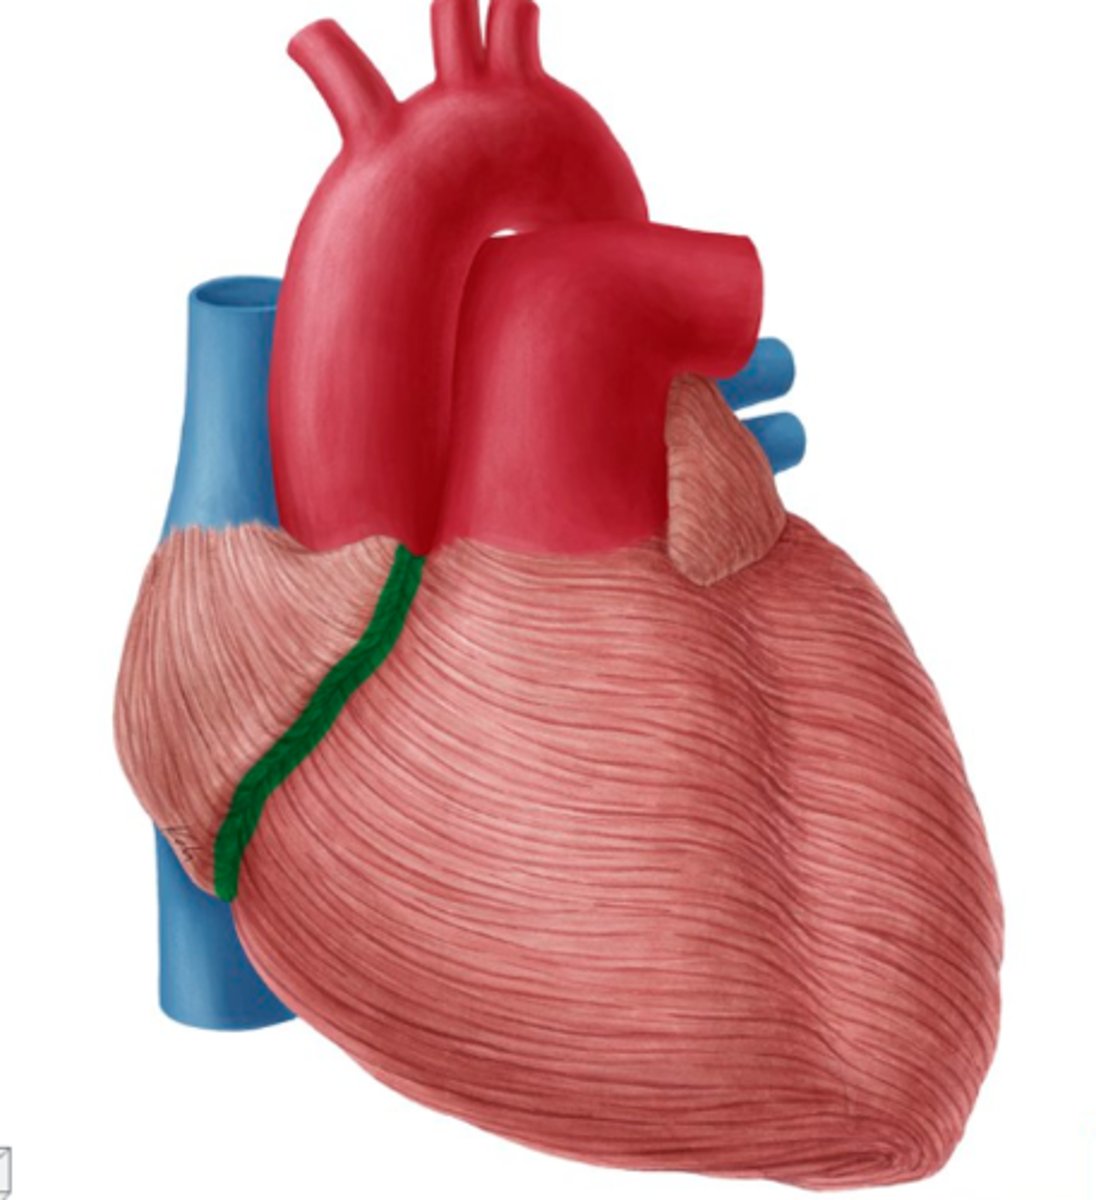

bruzda międzykomorowa przednia

anterior interventricular sulcus

Jak biegną bruzdy międzykomorowe?

od bruzdy wieńcowej w kierunku koniuszka serca

Co tworzą bruzdy międzykomorowe w okolicy koniuszka serca?

wcięcie koniuszka serca

wcięcie koniuszka serca

notch of cardiac apex